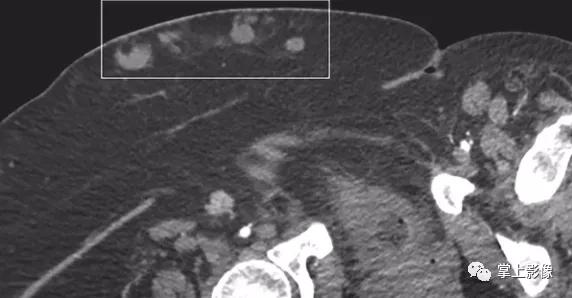

注射肉芽肿,46岁卧床不起妇女,每天皮下注射依诺肝素。CT显示多发注射肉芽肿(轮廓区)